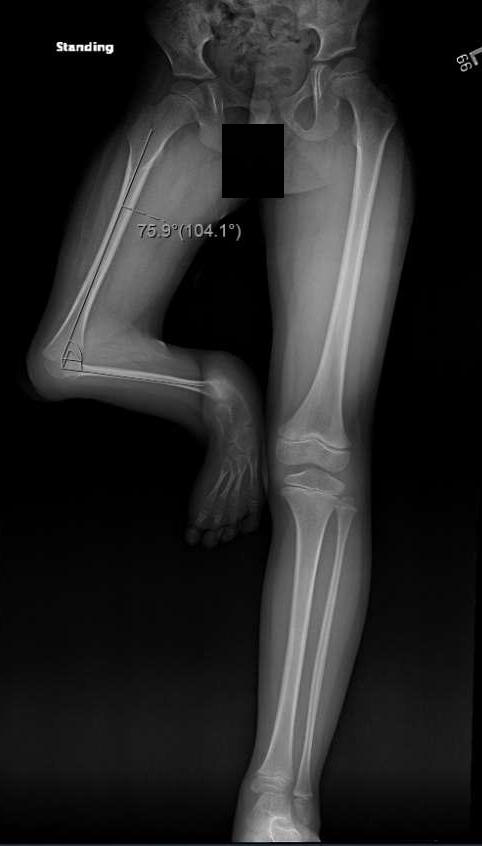

When Master “Fh” was born on March 23, 2015, in Riyadh, Saudi Arabia, his family’s joy was quickly overshadowed by the challenges they were about to face. Fh came into the world with a rare condition—complete tibial deficiency, Jones type 1A. His right leg had no tibia, and his foot was severely deformed, with his knee fixed in a position that made it impossible for him to walk like other children.

For years, Fh found a way to move using his right knee, despite its severe flexion of over 100 degrees, but the limitations were stark. His ankle and foot were completely nonfunctional, and X-rays revealed the absence of the tibia, along with a severely deformed foot. Reconstructive surgery was not an option.

‘’Two months after the surgery, Fh was ready for his first prosthesis. A through-knee prosthesis was custom-made for him, and the day he stood on it for the first time was unforgettable. For the first time in his life, he stood tall, balancing on both legs. He took his first independent steps, a moment that brought tears of joy to his parents and a sense of accomplishment to our team.” Mr. Imran recalled those moments.

A year later, Fh’s story took another extraordinary turn. At KFSH&RC, we introduced advanced 3D printing technology to prosthetics, and Fh became the first patient in Saudi Arabia to be fitted with a 3D-printed knee disarticulation prosthesis.

This new prosthesis was lighter, more comfortable, and highly functional. With it, Fh could do things that once seemed unimaginable—jumping, running, and playing like any other child his age. Watching him move with such freedom and joy was a testament to how far he had come.